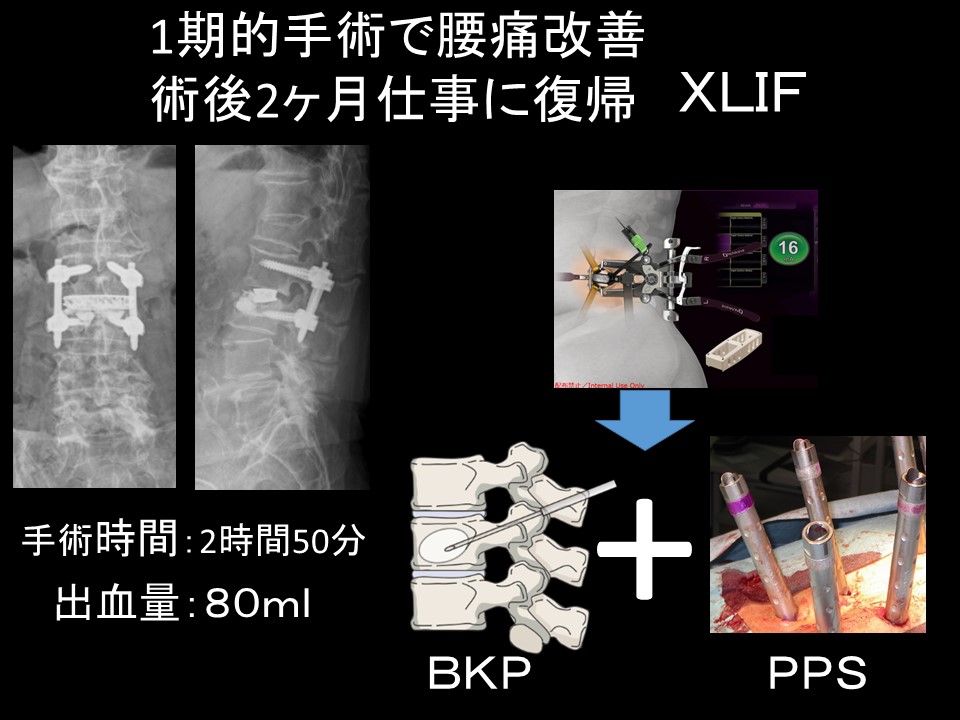

a3f1e84f-s.jpg。骨粗鬆症性椎体骨折に対する脊柱再建術 | 成尾整形外科病院。胸椎・腰椎の疾患 | 聖マリアンナ医科大学 横浜市西部病院。【送料込】 砕米24キロ 割れた米 飼料米 くず米 エサ米 鳥の餌。